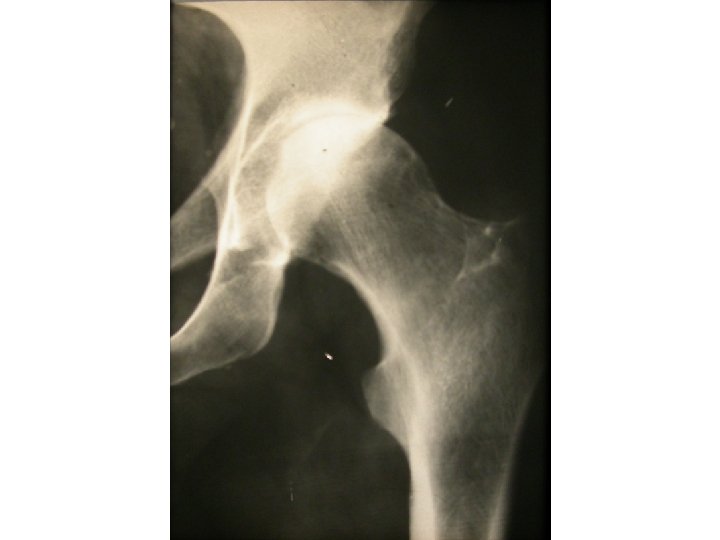

SEMIOLOGIE DE LA HANCHE J-P ESCHARD • Anatomie Articulation profonde Articulation très emboîtée mobilité

SEMIOLOGIE DE LA HANCHE J-P ESCHARD • Anatomie Articulation profonde Articulation très emboîtée mobilité réduite

SEMIOLOGIE DE LA HANCHE 3°Signes d’examen (signes physiques): Inspection: a) Étude de la marche

SEMIOLOGIE DE LA HANCHE 3°Signes d’examen (signes physiques): Inspection: a) Étude de la marche boiterie par esquive d’appui (visible et/ou audible) bascule du bassin (Trendelenbourg) b) Attitudes vicieuses réductibles ou non flessum RE

SEMIOLOGIE DE LA HANCHE 3°Signes d’examen (signes physiques): Etude des mouvements Mouvements passifs+++: le

SEMIOLOGIE DE LA HANCHE 3°Signes d’examen (signes physiques): Etude des mouvements Mouvements passifs+++: le coxogramme Mouvements combinés Mouvements actifs

SEMIOLOGIE DE LA HANCHE 3°Signes d’examen (signes physiques): Etude des mouvements Mouvements passifs+++: le coxogramme flexion/extension/abduction/adduction RE/RI Mouvements combinés Mouvements actifs : étude des muscles et des tendons: le moyen fessier++ 4° Examen régional: neurologique amyotrophie